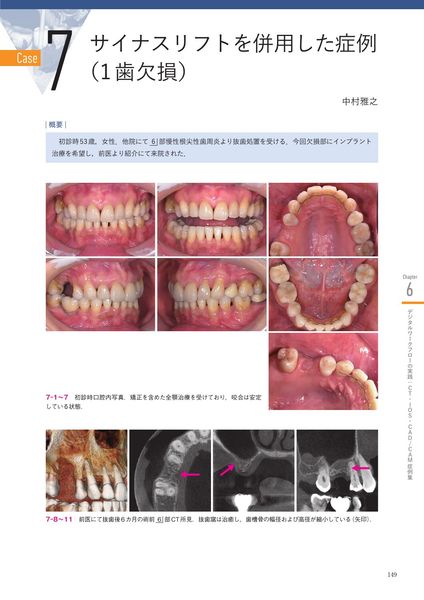

Chapter 6 デジタルワークフローの実践:CT・IOS・CAD/CAM症例集